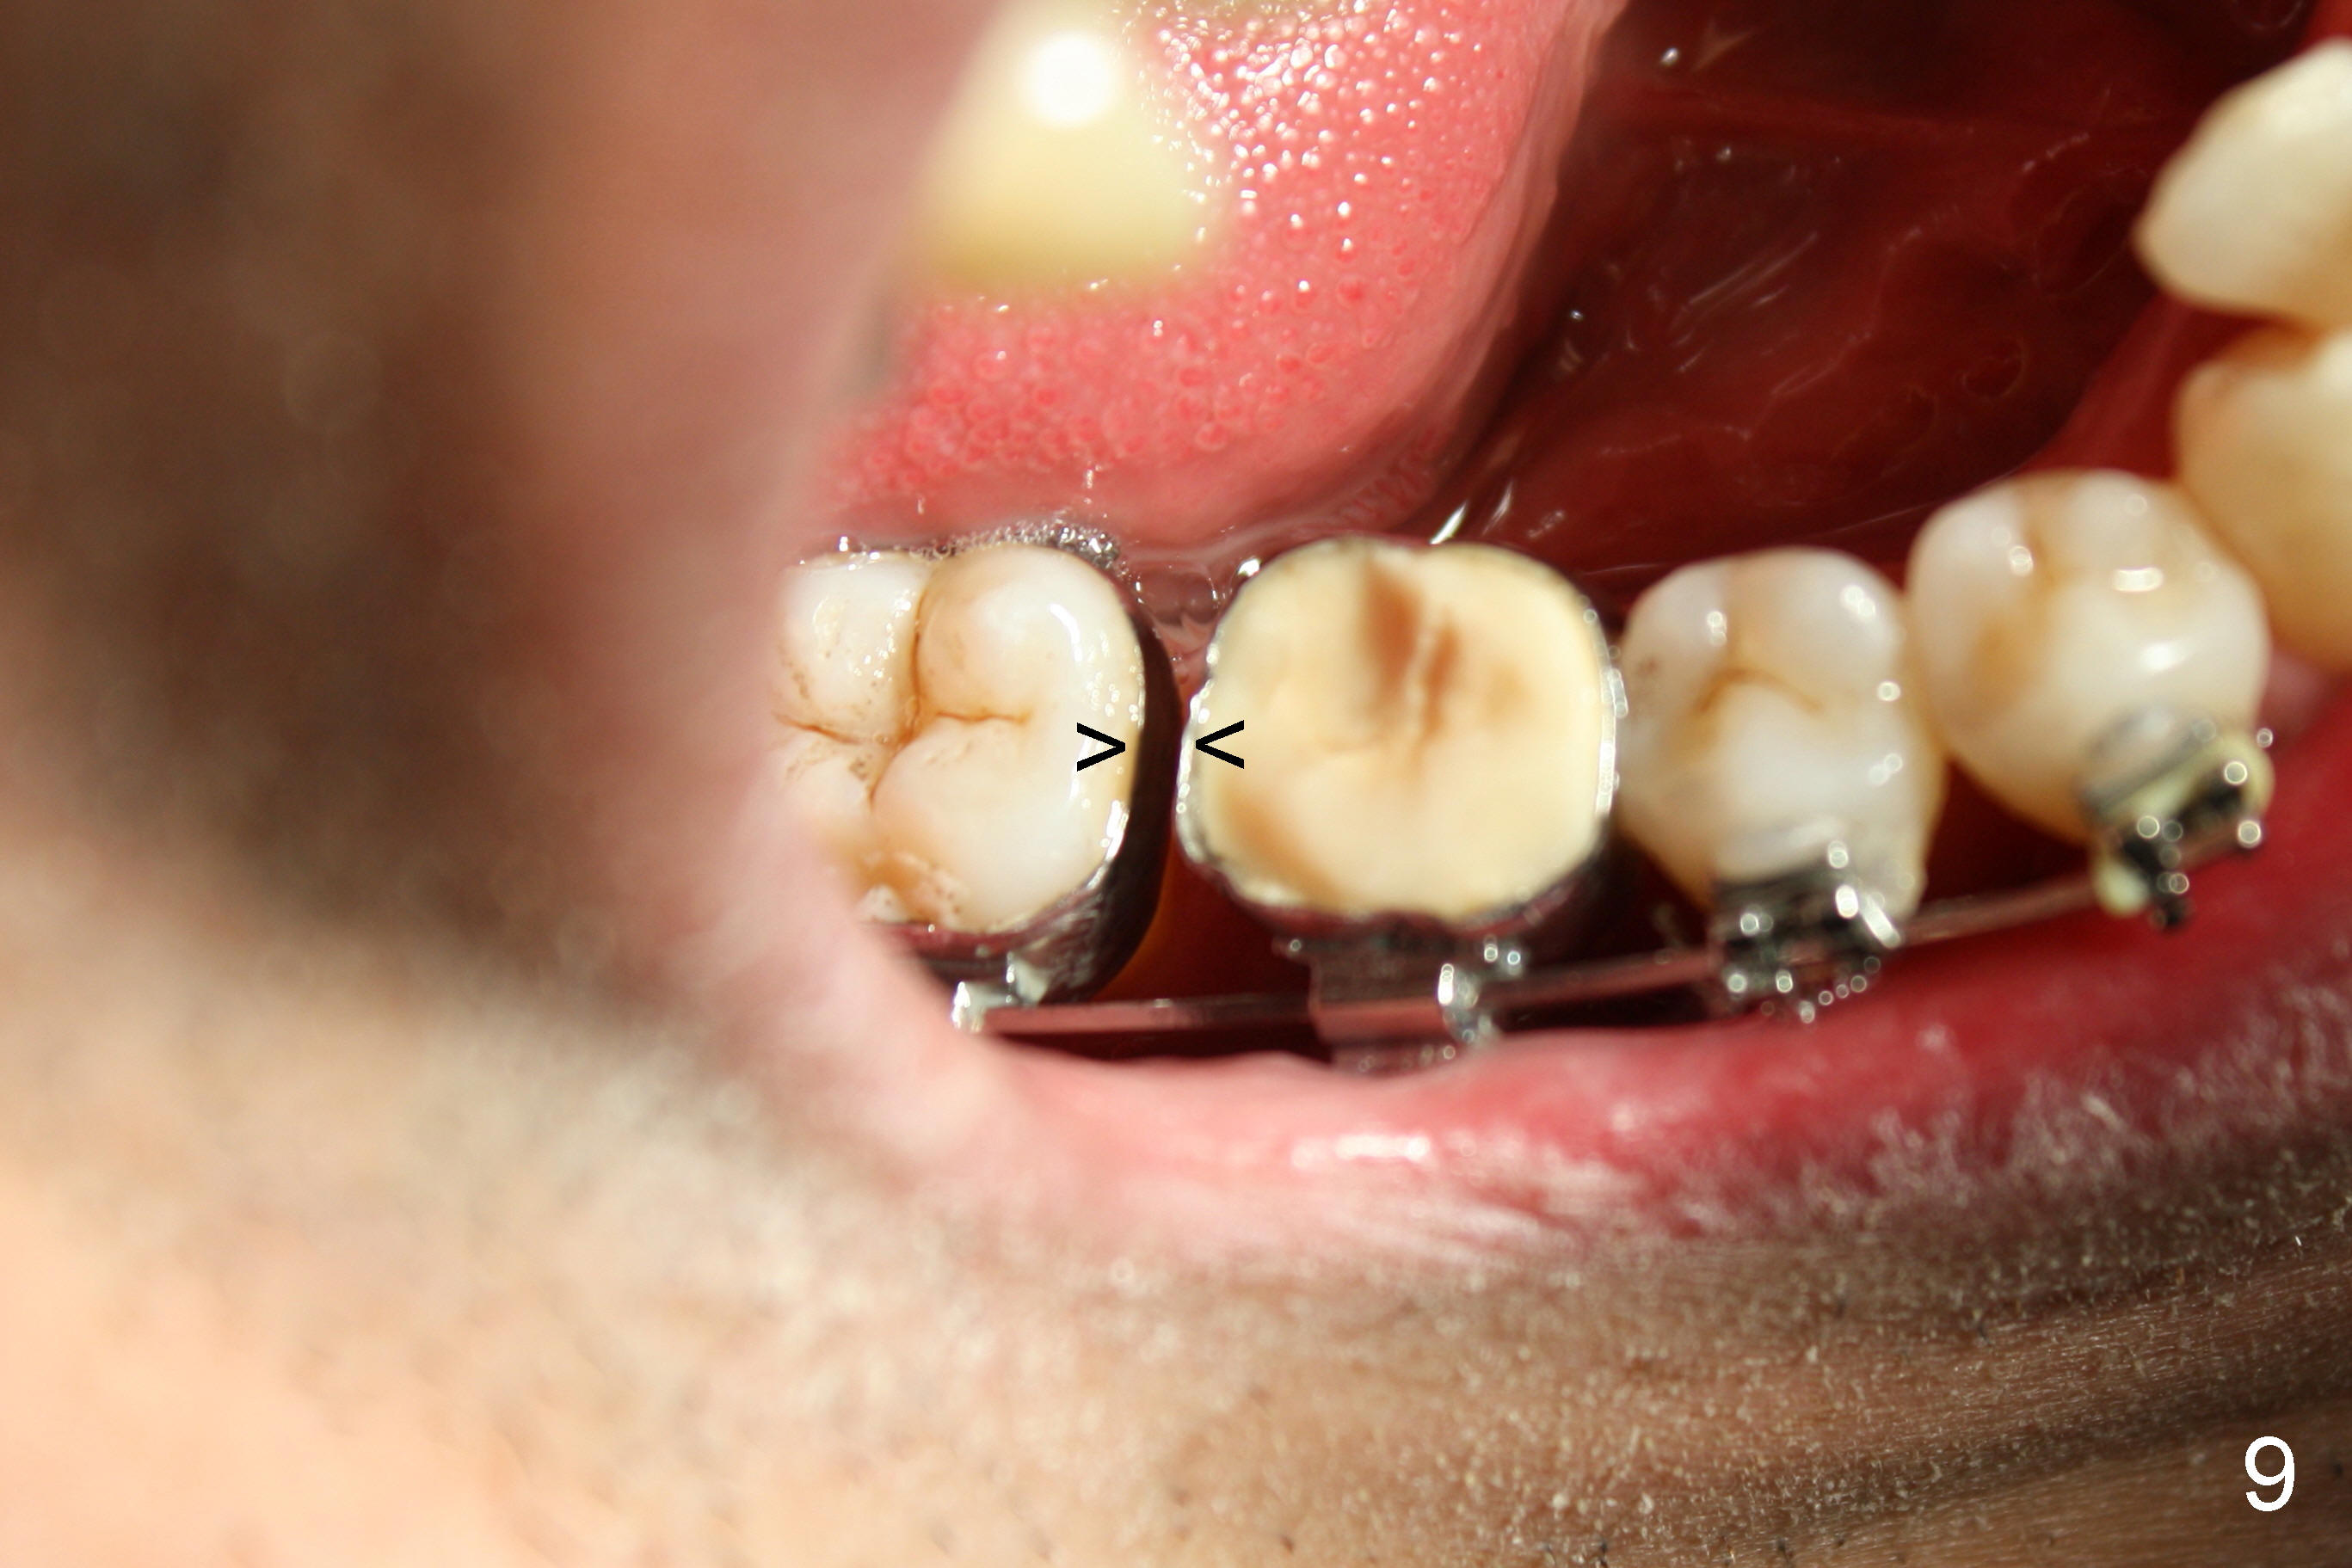

In 7 months, the right molar occlusion changes to Class I with normal overjet (Fig.8 mirror view). Class I posterior occlusion correction is evidenced by a gap between the teeth #30 and 31 (Fig.9 arrowheads) due to elastic retraction. There is no tension (bending) of wire between the teeth #2 and 3 in the final stage (Fig.10 arrowhead, as compared to Fig.7). A porcelain crown is subsequently cemented to the implant/abutment complex with occlusal equilibrium (Fig.11(mirror image) C). The remaining brackets and band are removed. Power chains in Fig.11 (arrowhead) were used to correct the rotation of the tooth #2 (Fig.10, bracket in the tooth was not well placed).